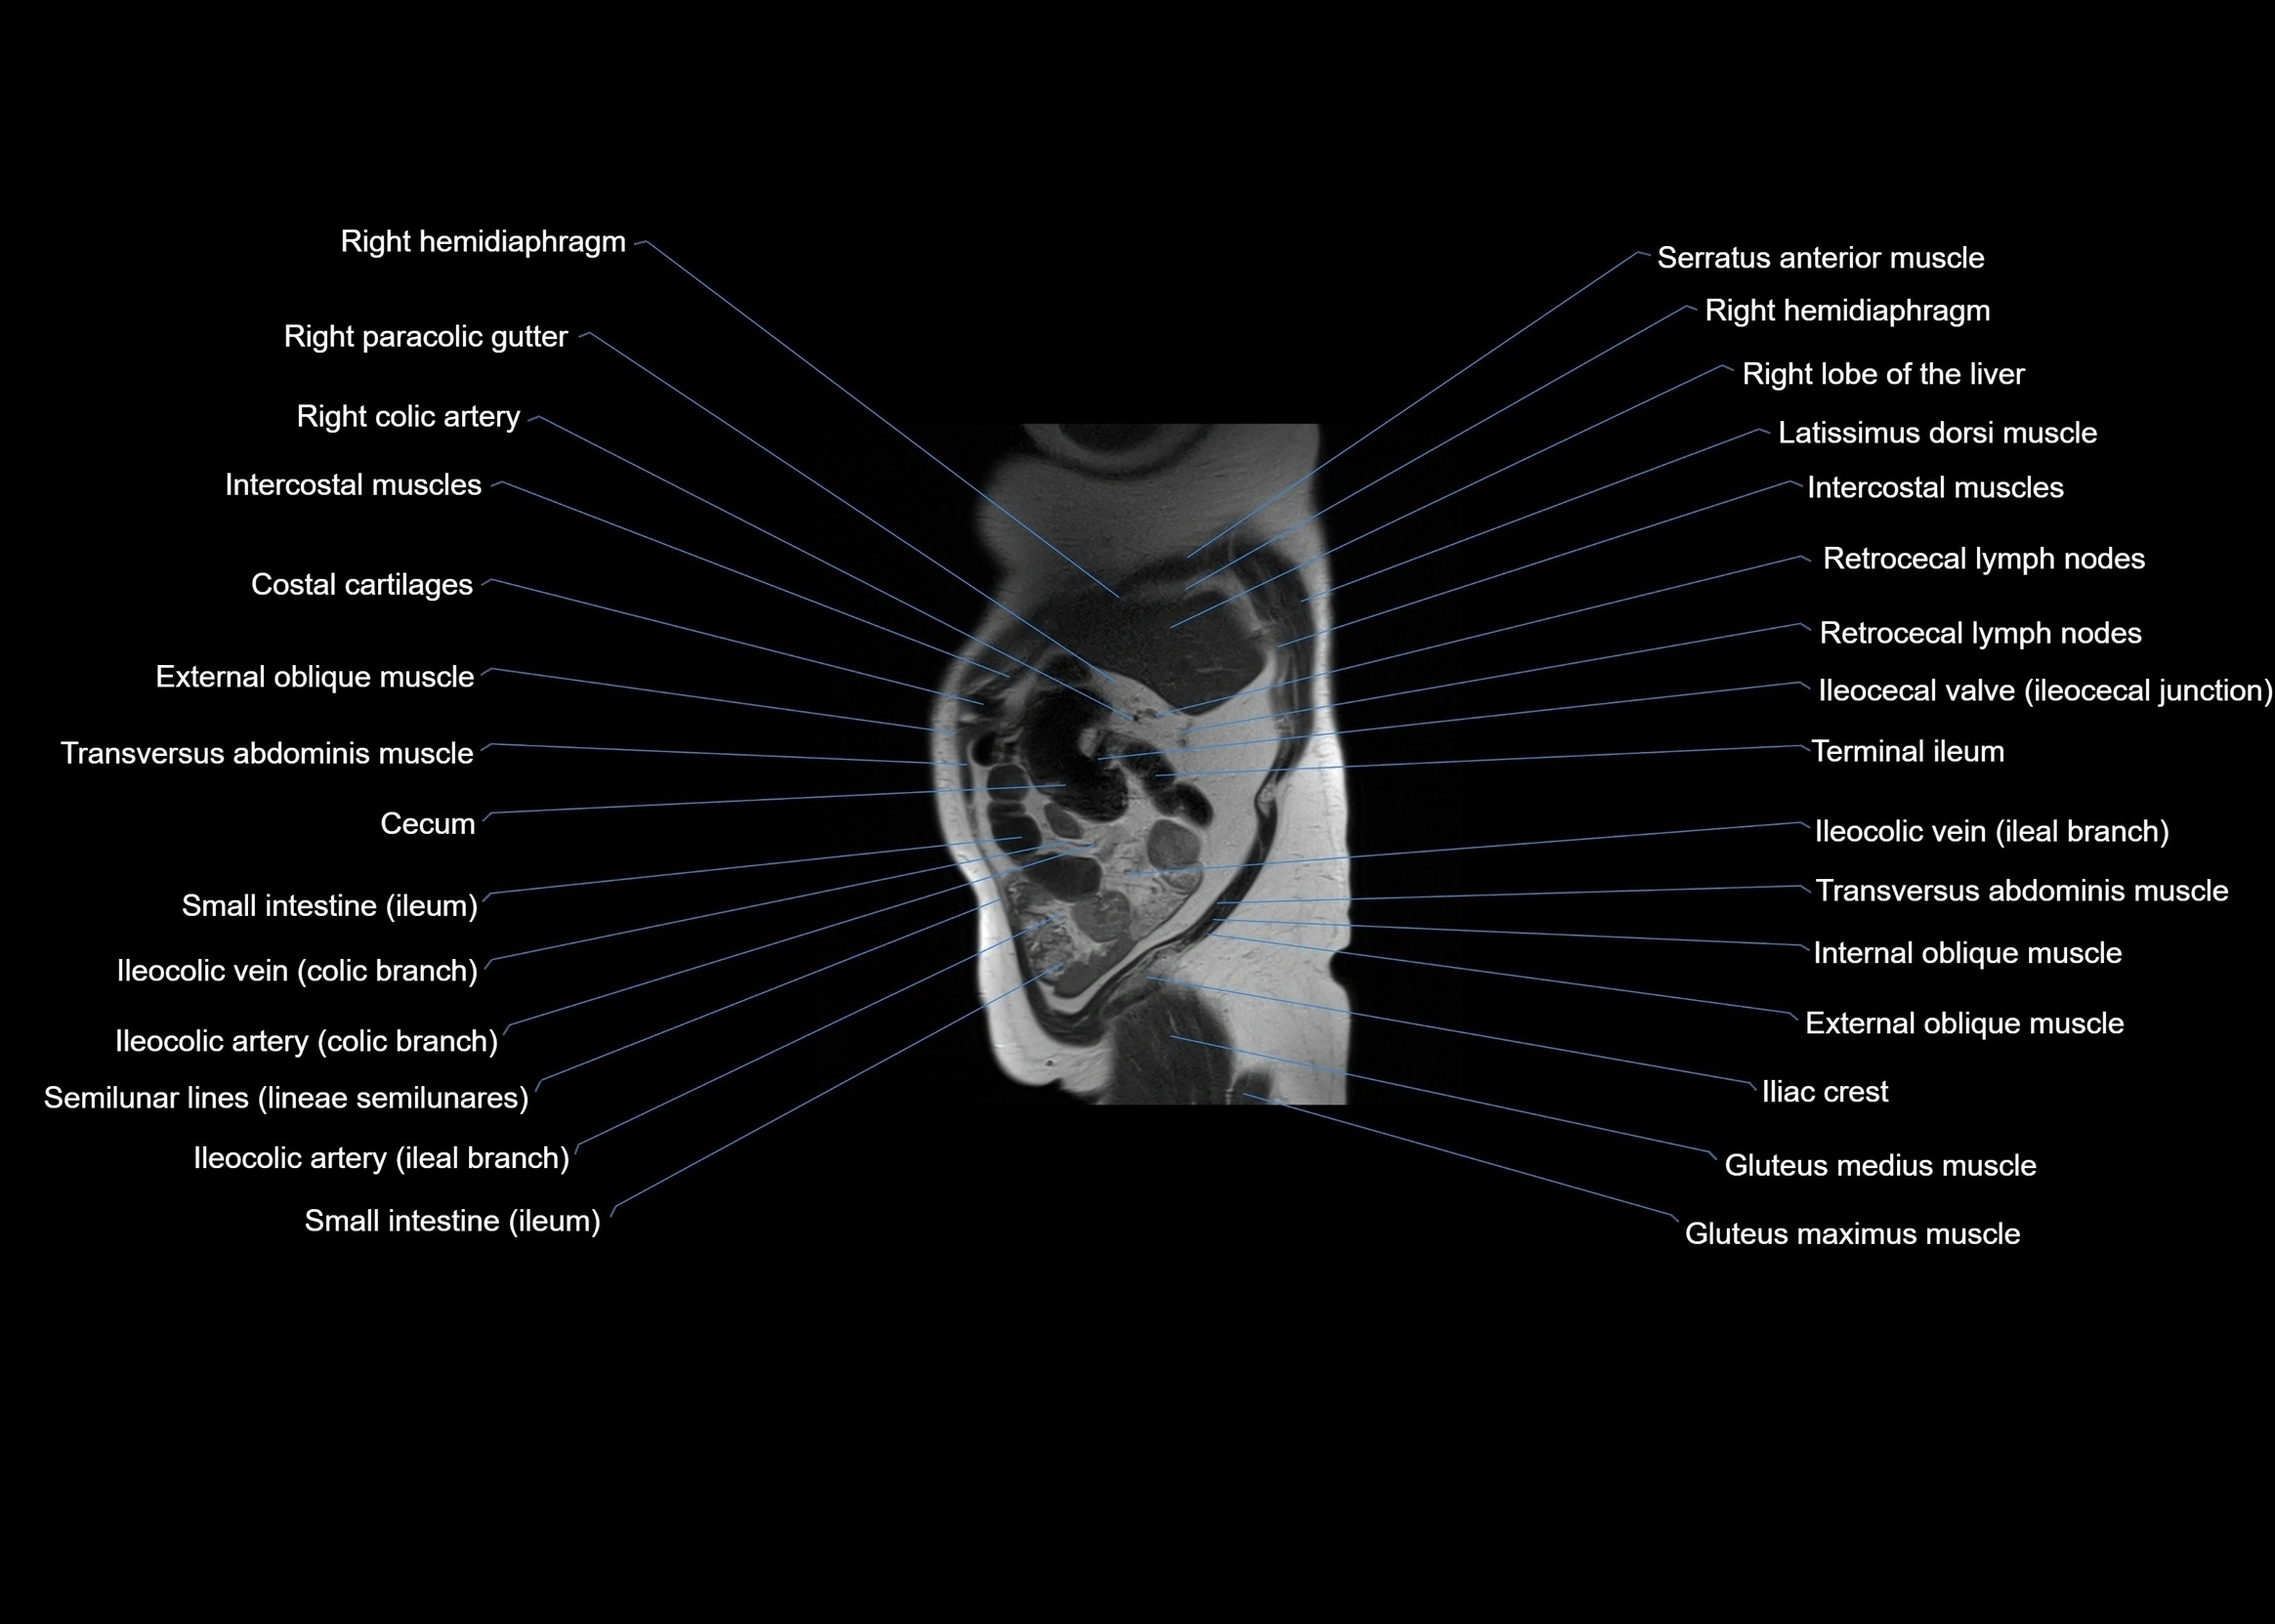

MRI images